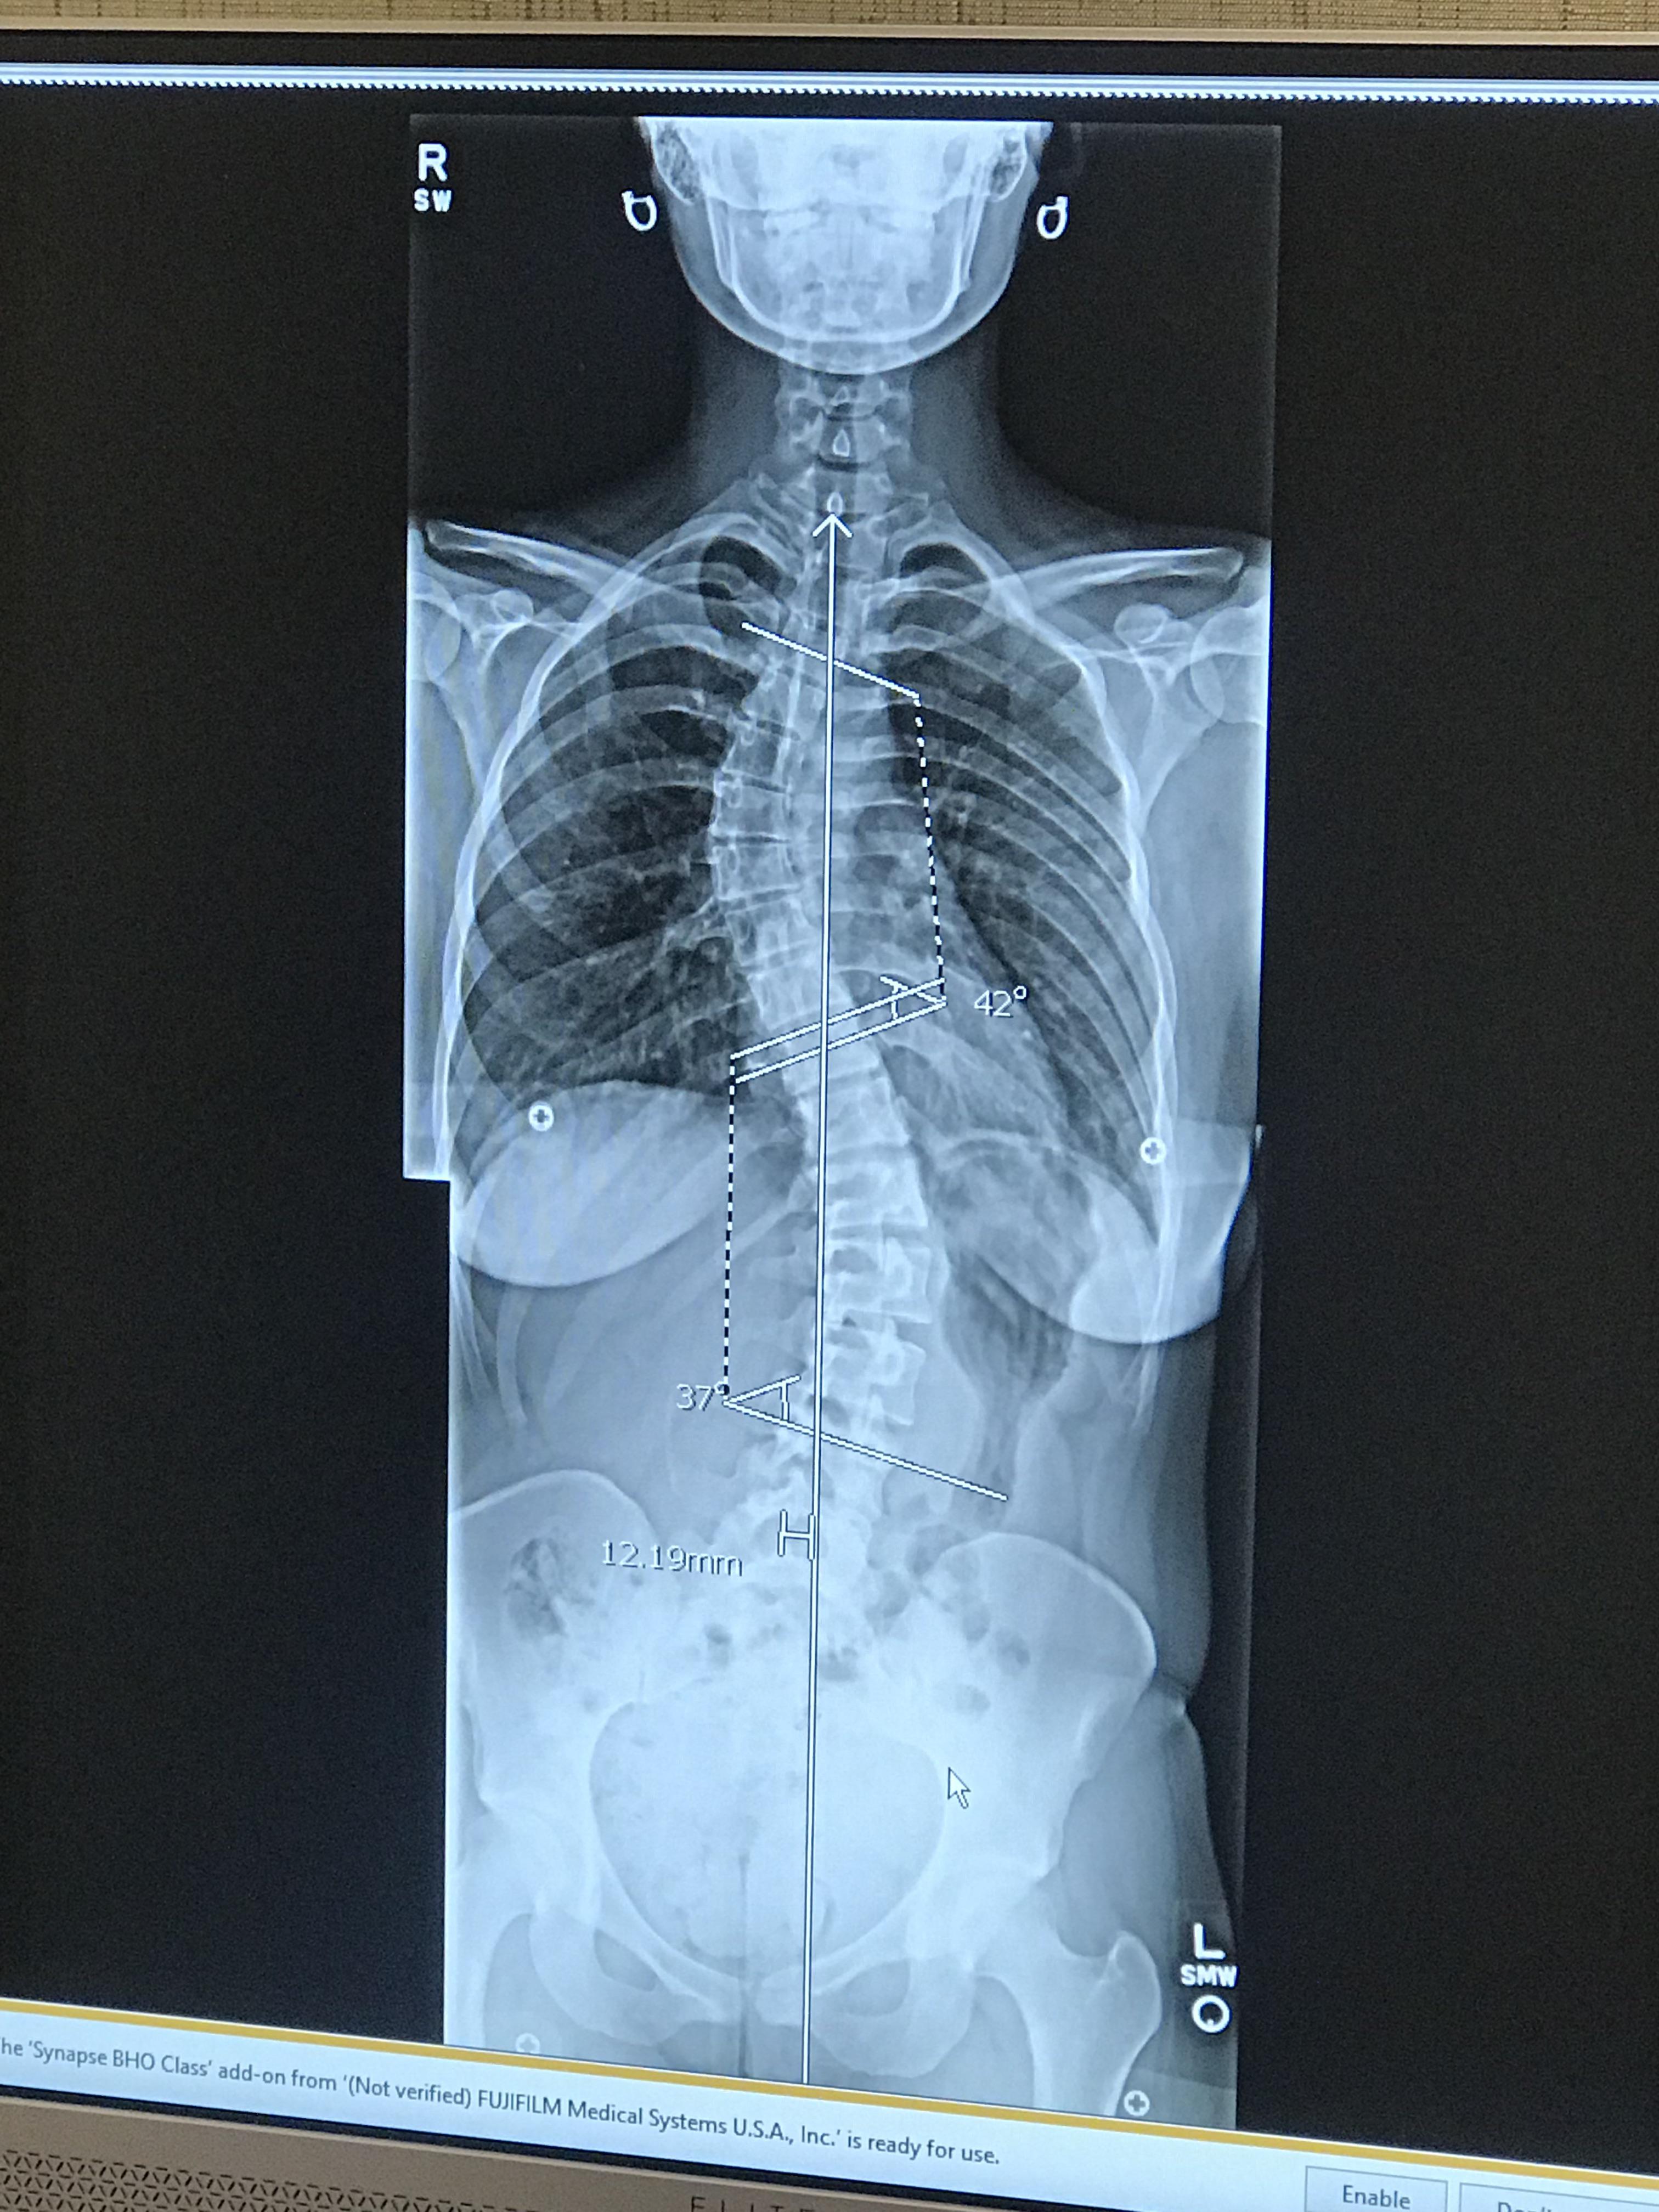

Chest Xray show fixed scoliotic deformity. The major scoliosis is

Chest Xray show fixed scoliotic deformity. The major scoliosis is Can Scoliosis Affect Your Chest Scoliosis can affect your breathing. However, in cases of cervical scoliosis, moderate. You may feel thoracic scoliosis pain in your back and shoulders. Chest pain is not commonly associated with scoliosis; But this typically happens only when the curve of your spine is severe enough to put pressure on your ribcage, making it difficulty for your. Idiopathic scoliosis is considered. Can Scoliosis Affect Your Chest.